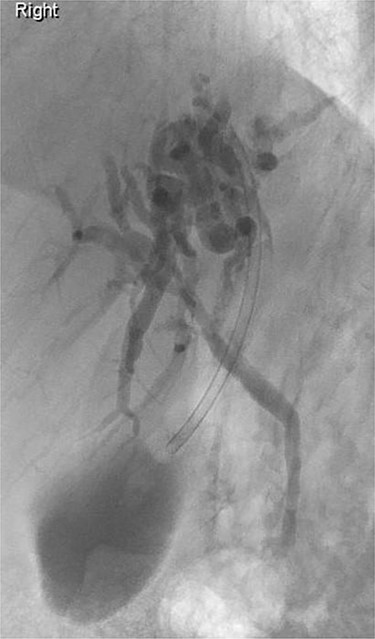

Further examination led to a diagnosis of DCBD with a separate left intra- and extrahepatic bile duct with ectopic drainage into the stomach. Magnetic resonance cholangiopancreatography (MRCP) revealed marked left intrahepatic duct (IHD) dilatation. The left IHDs were draining via an aberrant extra-hepatic bile duct into the pre-pyloric region. The left and right hepatic ducts did not communicate. It also demonstrated pancreatic divisum and multiple side branch intra-ductal papillary mucinous neoplasms (IPMN) (Fig. 3). Endoscopic retrograde cholangiopancreatography (ERCP) confirmed the MRCP findings but also revealed an intraluminal-filling defect in the left IHD (Figs 4 and 5).

MRCP: open arrow—the left IHDs drain via an aberrant (left) extra-hepatic bile duct into the pyloric region without communication with the (right) intra- and extra-hepatic bile ducts. Closed arrow—pancreatic divisum and side branch IPMN.